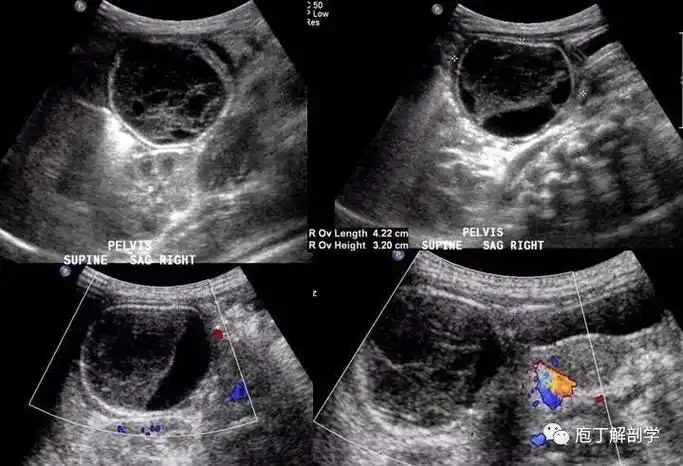

超声检查是诊断卵巢肿瘤蒂扭转的重要手段.

卵巢囊肿伴蒂扭转影像诊断及鉴别